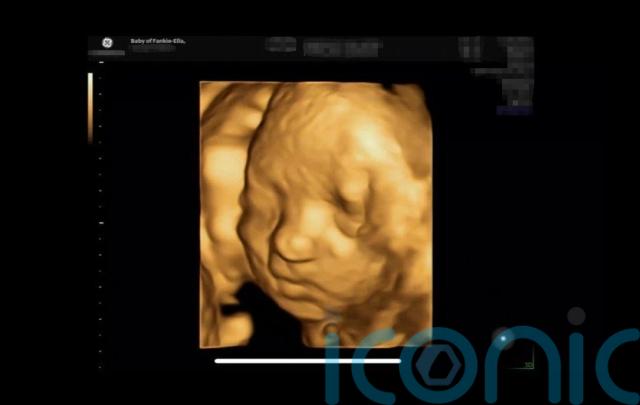

Frankie-Ella is now 35 weeks along in her pregnancy and in a letter seen by PA Real Life, her doctor described the situation as “a medical miracle”.

She and her baby are now being monitored with scans twice a week in the run-up to her due date in early January.

“They said the baby is going to be small and petite, I’m quite small anyway, and they’ve said she’s doing really well right now.”